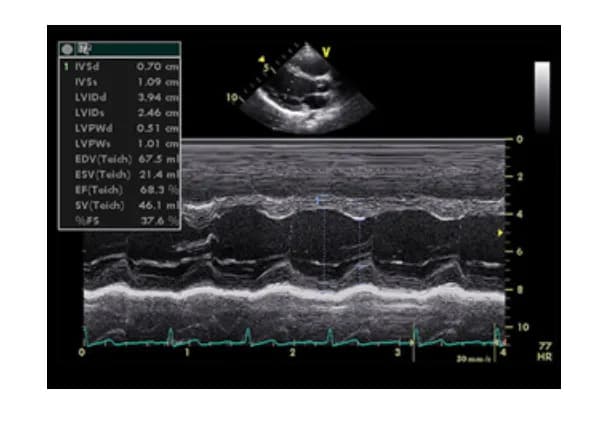

2. Siêu âm tim kiểu TM (M-mode)

Siêu âm tim kiểu TM (Time-Motion) là một kỹ thuật siêu âm tim одномерное, hiển thị hình ảnh chuyển động của các cấu trúc tim theo thời gian. Vì tim và các van tim vận động liên tục theo chu kỳ tâm thu và tâm trương, việc quét chùm tia siêu âm qua một thành phần giải phẫu của tim theo một vận tốc nhất định sẽ tạo ra hình ảnh dạng sóng, phản ánh sự thay đổi vị trí của cấu trúc đó theo thời gian.

• Độ chính xác cao: Do định vị được các thời điểm trong chu chuyển tim (tâm thu, cuối tâm thu, tâm trương, cuối tâm trương), siêu âm TM cho phép đo đạc các kích thước và chức năng co bóp của tim một cách chính xác.

Ứng dụng của siêu âm tim TM:

• Đo đường kính thất trái cuối tâm trương (LVIDd) và cuối tâm thu (LVIDs): Từ đó tính toán chức năng tâm thu thất trái (EF - Ejection Fraction).

• Đo kích thước thất phải.

• Đo độ dày của thành thất trái ở tâm trương (IVSd và LVPWd) và tâm thu (IVSs và LVPWs).